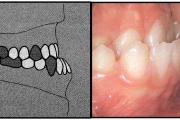

Ravijärgne seis. Jäävhammas on täielikult lõikunud.

Esimese jäävmolaari ektoopiline lõikumine